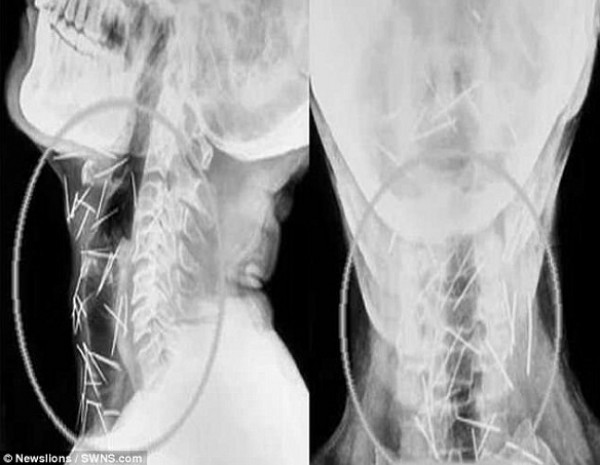

أثار رجل هندي حيرة الأطباء، بعد أن عثروا على أكثر من 150 دبوساً منتشرة في جميع أنحاء جسده، دون أن يعرفوا كيف وصلت إلى هناك.

واضطر باديرلال مينا (56 عاماً) لزيارة 6 مستشفيات والخضوع لثلاث عمليات جراحية، لإزالة الدبابيس من ذراعيه وقدميه وعنقه، وحتى الآن تمت إزالة 91 دبوساً، البعض منها كان صدئاً للغاية، بعد أن تركت داخل جسده منذ عدة أشهر، بحسب صحيفة ديلي ميل البريطانية.

ويصر مينا وهو من كوتا شمالي الهند، أنه لم يغرس أياً من هذه الدبابيس داخل جسده، ولا يعرف كيف وصلت إليه، في حين يقول الدكتور لاليت موهان بارشار إن عدم إصابة مينا بأية أضرار دائمة أشبه بالمعجزة.

وأضاف الدكتور بارشار الذي أجرى العمليات الجراحية للمريض "شكل إخراج الدبابيس من جسمه بأمان تحدياً كبيراً بالنسبة لنا، خاصة وأن بعضها كان مغروساً في الرغامى والمري، وحتى في الشريان السباتي الذي يحمل الأوكسجين إلى الدماغ".

وكان مينا راجع المستشفى للمرة الأولى، وهو يشكو من آلام في القدم اليسرى، ووجد الأطباء نحو 75 دبوساً مغروسة في مناطق متفرقة من جسده، وفقد نحو 30 كيلوغراماً من وزنه، أثناء محاولته العثور على جراح على استعداد للمخاطرة بإزالة هذه الدبابيس.

وفي نهاية المطاف، قبل المعهد الآسيوي للعلوم الطبية التعامل مع الحالة، وعلى مدى 3 عمليات جراحية، تمت إزالة أكثر من 90 دبوساً من جسد مينا، ويقول الأطباء إنه بصحة جيدة، ولا يزال يتعافى من آثار العمليات الجراحية المعقدة.